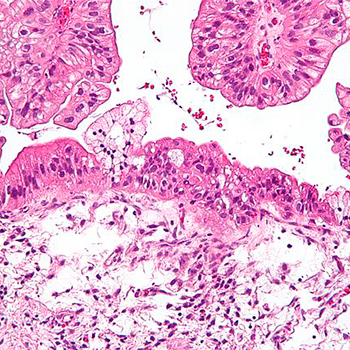

Tumor de Krukenberg del ovario: estudio clínico patológico ... 😈